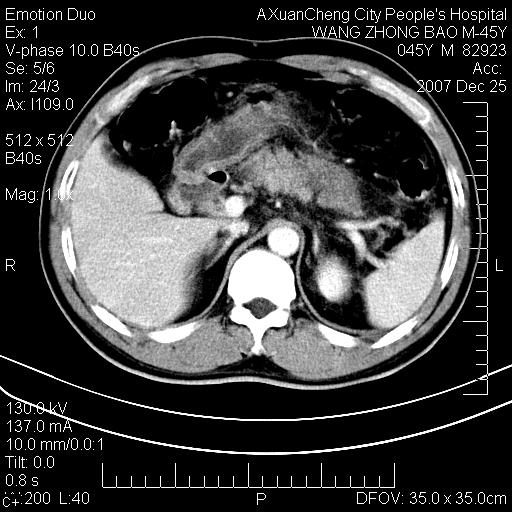

以下是引用卜一在2007-12-25 14:07:00的发言:[br]胰头钩部略增大,与十二指肠壶腹部关系密切,其内明显见软组织密度肿块,明显强化,但肠壁较光滑 柔软。考虑:炎性增生!建议消炎后复查!待除外壶腹部腺癌!

以下是引用zjzjr在2007-12-25 13:35:00的发言:[br]考虑正常的十二指肠乳头部,建议胃镜检查.

以下是引用qiuleiyu在2007-12-25 18:14:00的发言:[br]胰腺增大,周边渗出改变,肾前筋膜明显增厚,示少量积液.胆囊壁毛糙,周边少许渗出,胆总管壁厚,异常强化,然扩张不明显.结合病程急短;考虑;胆管炎,胆囊炎,胆源性胰腺炎可能大,请结合实验室检查及随访.

以下是引用lisihao在2007-12-25 14:23:00的发言:[br]急性水肿型胰腺炎[br]依据:1、胰腺弥漫性肿大,边缘稍毛糙;[br] 2、双侧肾周筋膜增厚,尤以左侧为甚(重要征象)[br] 3、双侧后胸膜增厚(刺激性炎症);[br] 4、结合病史,查血尿淀粉酶应该可以确诊。